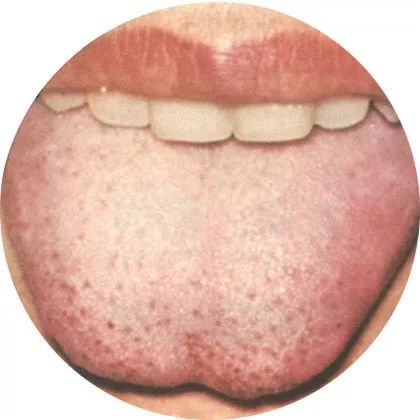

4淡白舌:体内虚汗

舌质淡白而胖嫩,是阳气虚衰所致;

舌质淡白而瘦小,是气血亏虚所致。

淡白舌而属于机体虚证、寒证之舌象。